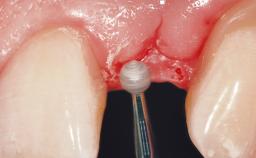

Immediate Placement of an Implant in a Maxillary Left Central Incisor Site

Placement Protocol Immediate implant placement

Soft Tissue Grafting Simultaneous

Bone Augmentation Horizontal|Simultaneous

Augmentation Materials Xenogenous|Membrane